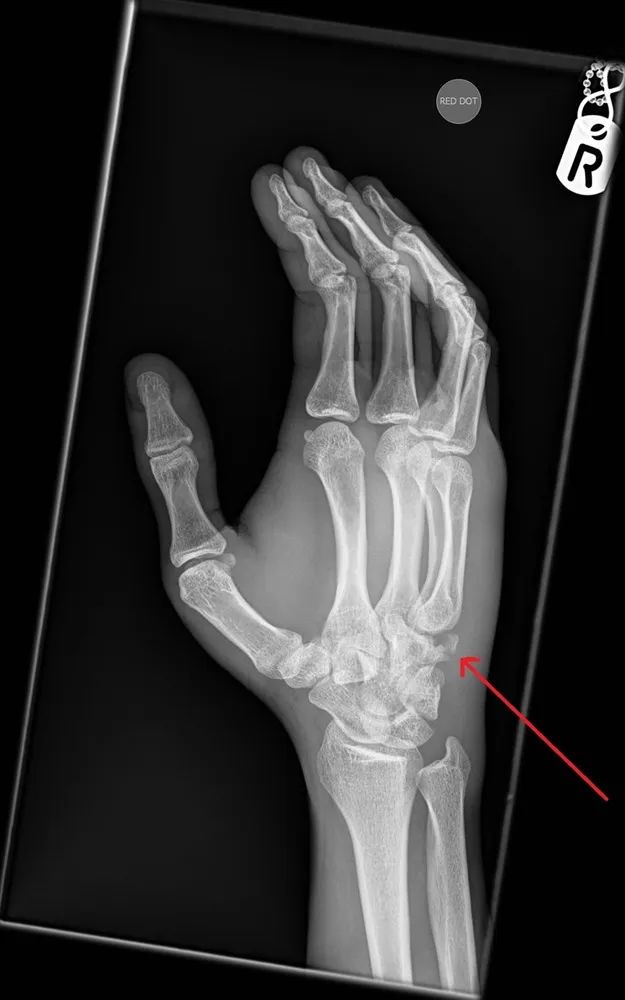

把这幅示意图发上来,大家进一步看一看。

右手斜位片,红色箭头提示钩骨骨折。

据报道,腕骨骨折中2%为钩骨骨折。钩骨骨折中,钩骨钩突骨折比钩骨体骨折更为常见。钩骨骨突是一个骨性突出物,有直接受压骨折的危险。钩骨骨折多见于掌击硬物(如手掌大力拍墙)所致。